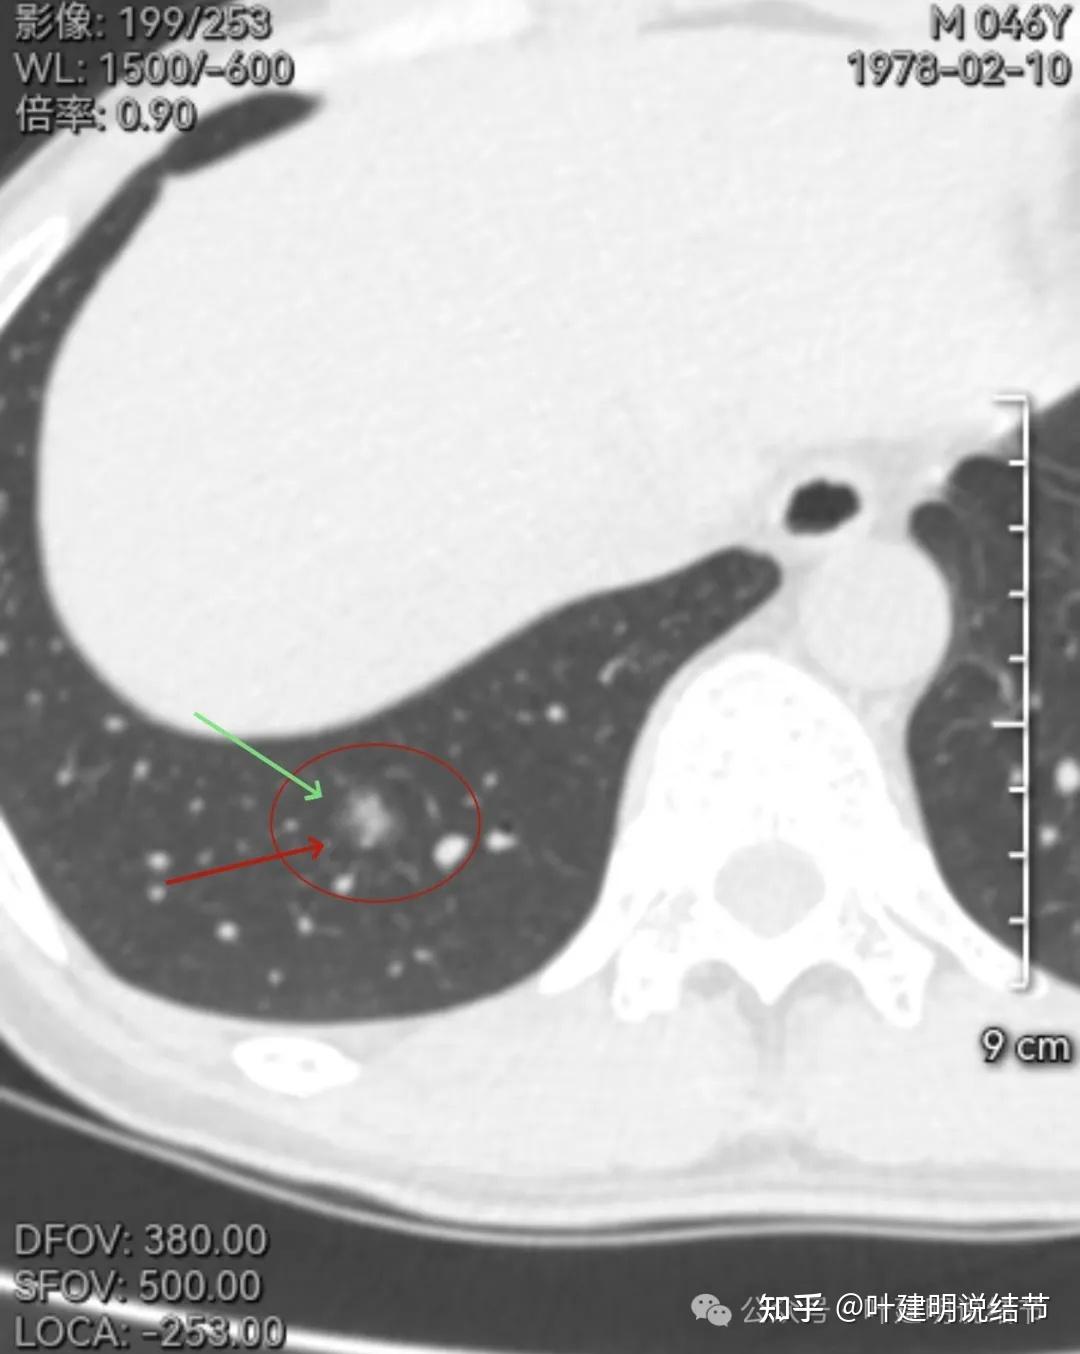

19mm的混合磨玻璃结节复查没有缩小,适时楔形切除小手术可以根治